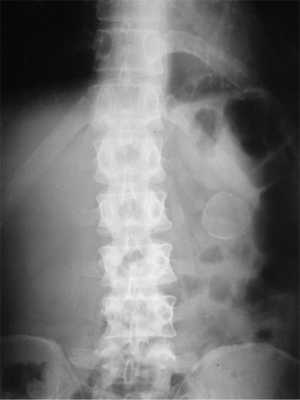

По данным спиральной компьютерной томографии брюшной полости с внутривенным контрастированием определяется расширение поперечной ободочной кишки с пролабированием в ее просвет эксцентрично расположенной петли восходящей и слепой кишок с утолщенными стенками вместе с брыжейкой и образованием жировой плотности размером 66×42×44 мм. Дистальный край образования визуализируется практически на уровне селезеночного угла. Стенки поперечной ободочной и нисходящей кишок на уровне селезеночного угла тонкие, не изменены. Имеющаяся картина соответствует образованию жировой плотности — липоме слепой кишки, осложненной толстокишечной инвагинацией слепой и восходящей кишок в просвет поперечной ободочной кишки (рис. 1).

Рис. 1. Компьютерные томограммы в сагиттальной (а), коронарной (б) и аксиальной (в) проекциях.

На основании клинического и лучевого методов обследования установлен диагноз: липома слепой кишки. Частичная инвагинационная толстокишечная непроходимость.